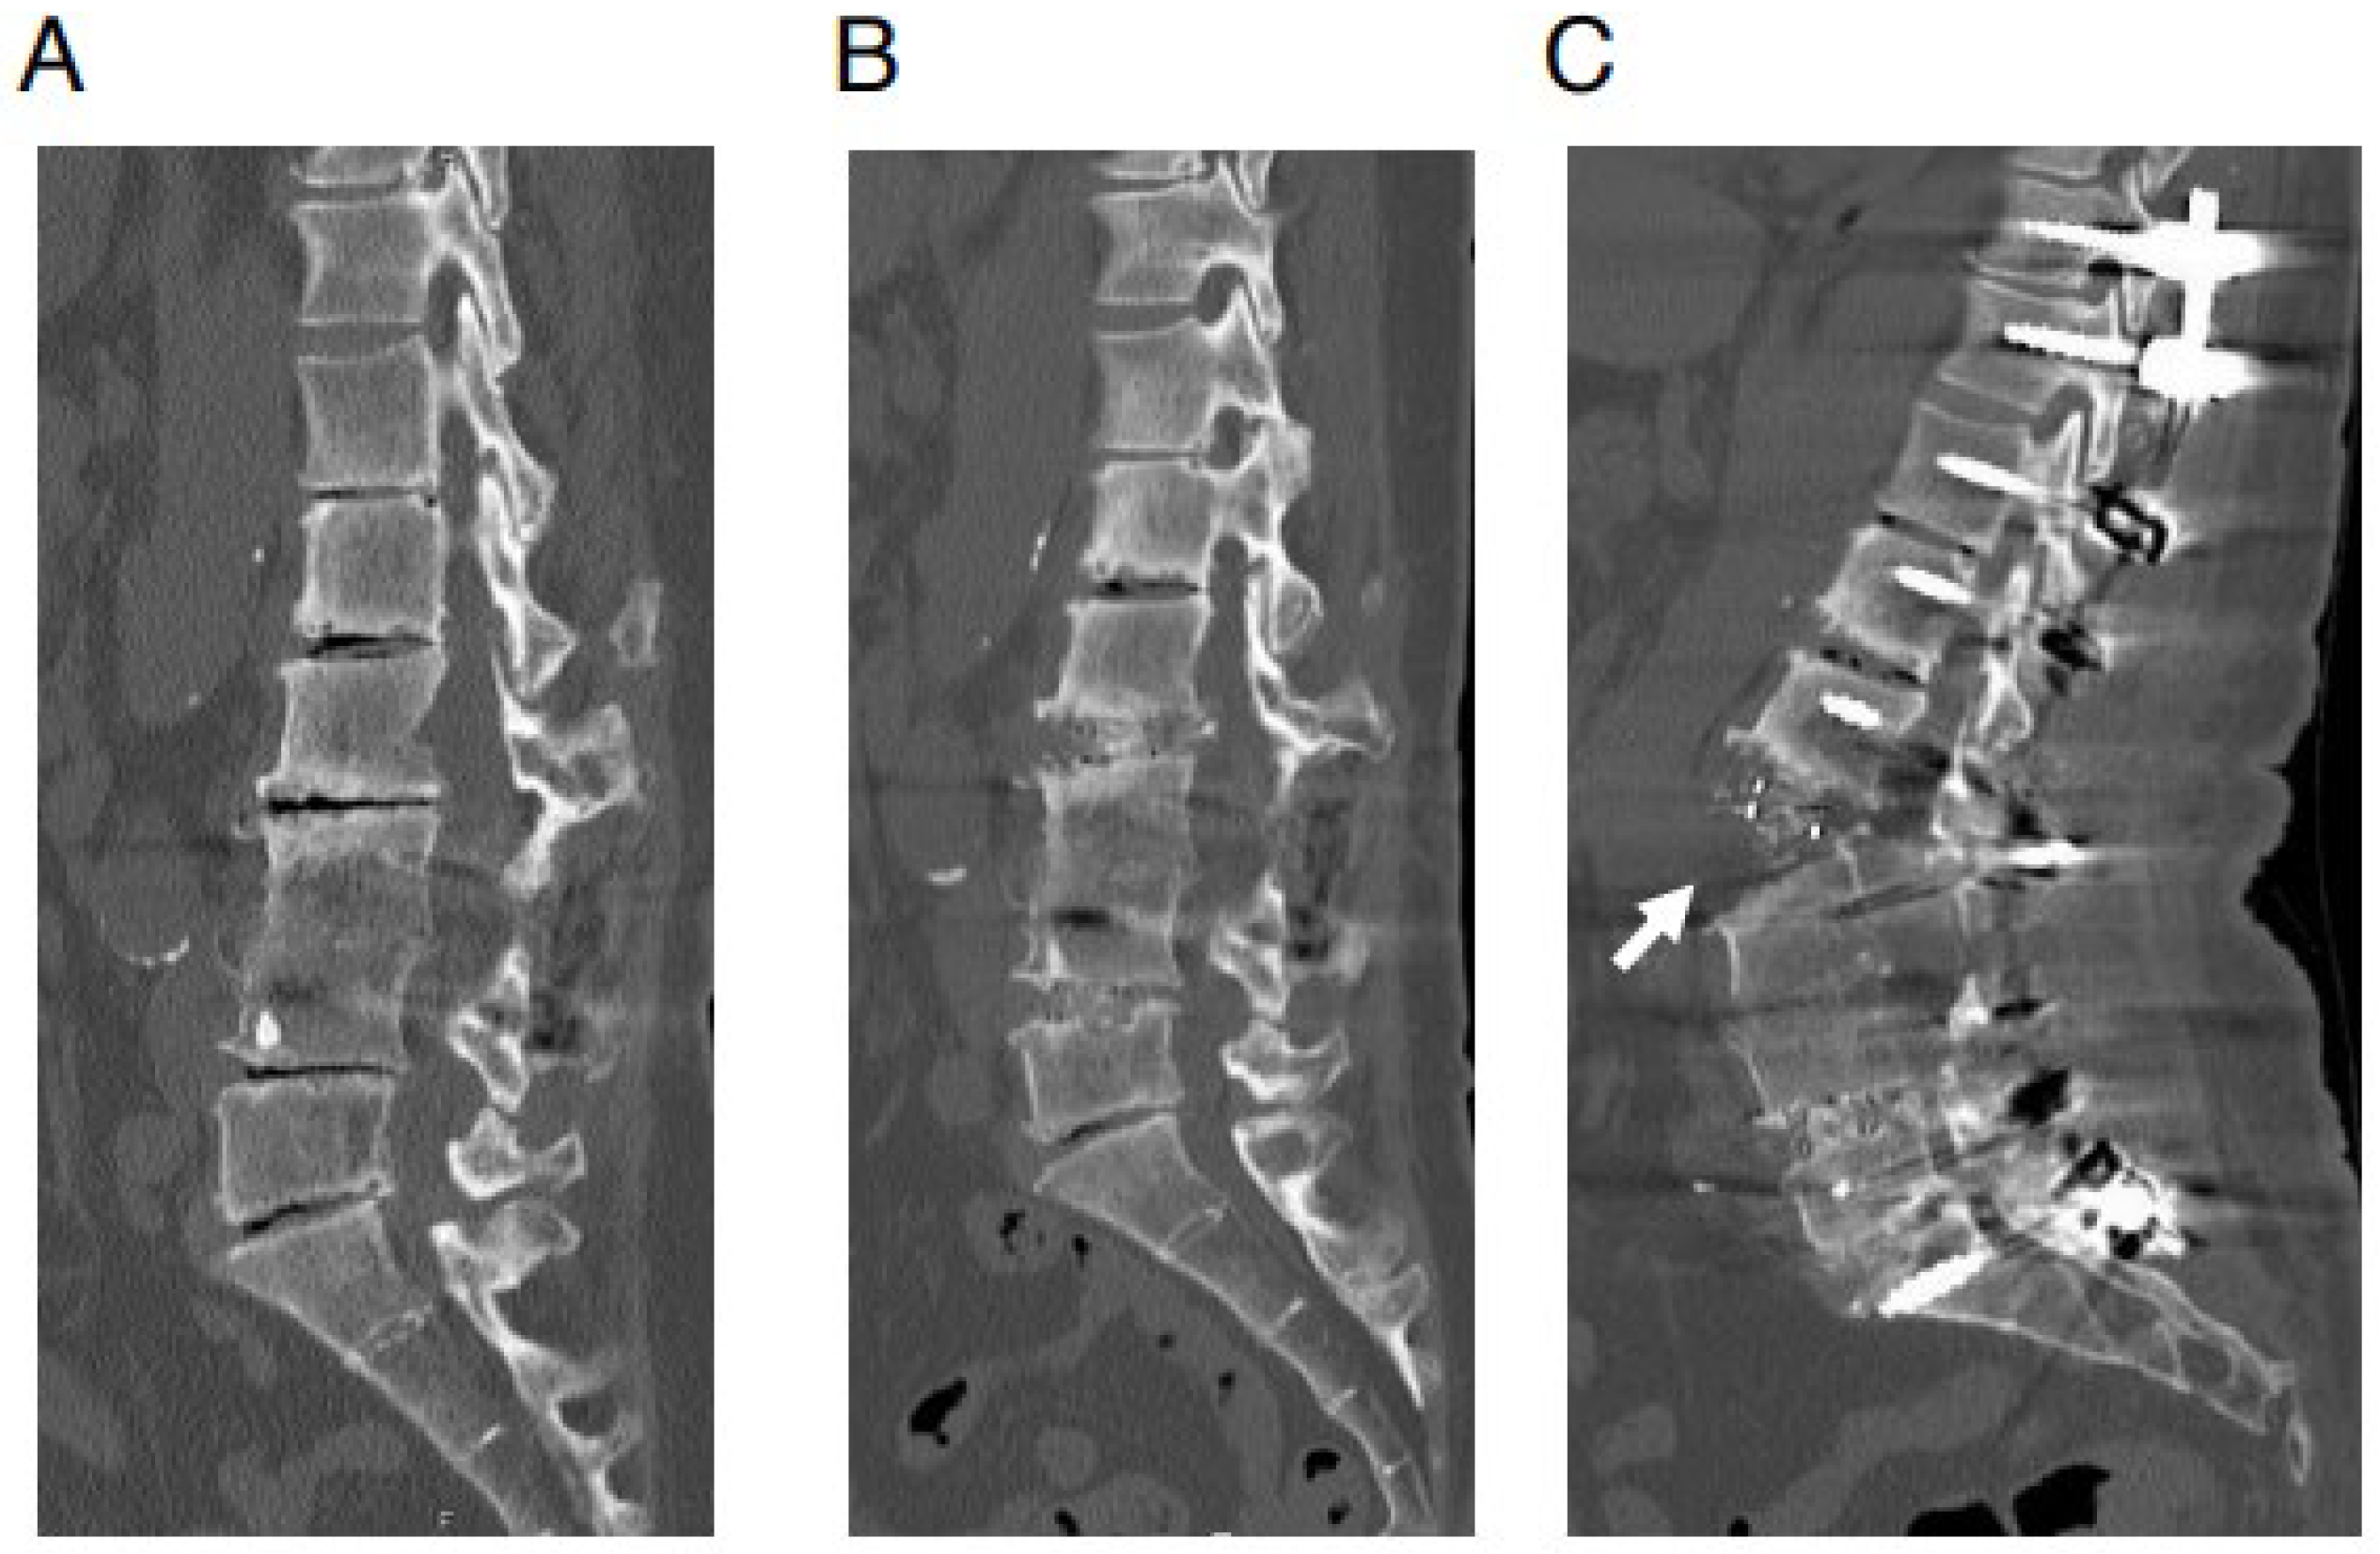

However, we currently have unresolved new issues. One of the new issues is an anterior longitudinal ligament (ALL) rupture which is occasionally observed during the posterior correction procedure for ASD using LLIF (Figure 1) [14,15,16]. The possibility of pseudoarthrosis increases at the level of ALL rupture; therefore, it is very important to prevent it. However, the mechanism of ALL rupture during the posterior correction procedure remains unknown.

Figure 1.

ALL rupture during posterior correction procedure: representative case. A 64-year-old woman with adult spinal deformity. In this case, postero-lateral fusion had been performed at L3/4 level previously at another hospital. Preoperative and postoperative reconstructed sagittal views of CT images. (A) Preoperative CT image. (B) CT image after OLIF (L2/3·L4/5). (C) CT image after posterior correction procedure. In this case, surgery was performed when only the less lordotic (6°) OLIF cages were available. Anterior longitudinal ligament rupture (white arrow) is observed after the posterior correction procedure.

The maximum lordotic angle of the OLIF cage is currently 12 or 15 degrees depending on the manufacturing company. However, when the OLIF was initially introduced, the maximum lordotic angle was 6°. When using only the less lordotic 6° OLIF cages, ALL rupture (during the posterior correction procedure) was more frequently observed than in later periods when more lordotic cages were available (Figure 1). Therefore, an LLIF cage with two different lordotic angles (6° and 12°) was employed for comparison in the FEA of the current study. We consider that ALL rupture during a posterior correction procedure is a multifactorial phenomenon. We intended to simplify the experimental method to evaluate the impact of each factor one by one. Additionally, FEA is an effective method for analyzing the cause of ALL injuries during posterior correction procedures in a one-by-one manner. The aim of this study is to evaluate the impact of the lordotic angle of the LLIF cage on the burden to ALL during a posterior correction procedure.

When LLIF was introduced initially, only less lordotic cages were available, and ALL rupture with posterior correction procedures was more frequently experienced compared with later periods when more lordotic cages were available (Figure 1). Therefore, we performed FEA regarding the mechanism of ALL rupture with a posterior correction procedure using two different lordotic angle LLIF cages. Furthermore, we developed two different types of FEA models that mimicked the compression procedures for common lumbar degenerative diseases and posterior correction procedures for ASD.